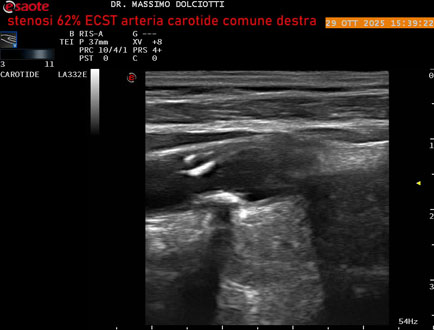

Data inserimento: 30/10/2025

Ecografia del: 29/10/2025

Strumento: Esaote MyLab Eight

Sonda: Lineare Multifrequenza 3-11 MHz

Età Paziente: F 75 anni

Motivazione dell'esame: controllo in pz con ateromasia carotidea ed ipercolesterolemia.

Commento all'esame: le immagini ed il video documentano all'arteria carotide comune destra placca disomogenea tipo 3 della classificazione di Gray Weale, che determina stenosi del 62% calcolato con metodo ECST.

Conclusioni: stenosi del 62% ECST dell'arteria carotide comune destra (62% ECST stenosis of the right common carotid artery).

Presentazione: Dr. Massimo Dolciotti - Ancona

Elaborazione digitale: Andrea Dini - Ancona